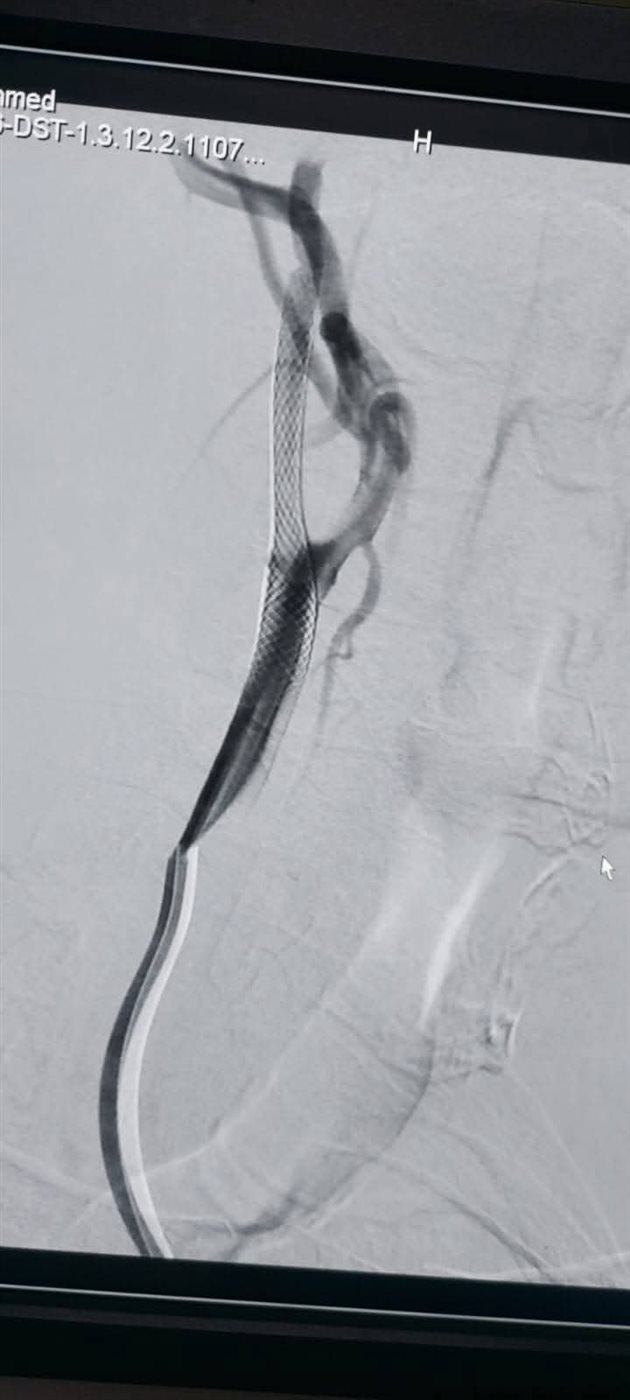

وكان المستشفى الرئيسى بجامعة أسيوط قد استقبل مريض يبلغ من العمر 65 عاما، يعانى من جلطات متعددة بالمخ نتيجة ضيق حرج بالشريان السباتي، وبعد إجراء الفحوصات اللازمة تقرر ضرورة التدخل بالقسطرة.

وتشكل الفريق الطبي من جامعة أسيوط الذي جاء برئاسة الدكتور مصطفى هاشم أستاذ الأشعة التشخيصية والتداخلية والقسطرة المخية، يعاونه الدكتور محمود رفعت مدرس واستشاري الأشعة التشخيصية والقسطرة المخية، والدكتور محمود نجيب مدرس واستشاري الأعصاب والقسطرة المخية، والطبيب عبد الرحمن عمر مدرس مساعد الأشعة التشخيصية والتداخلية.

وتعد القسطرة المخية واحدة من أهم التطورات الطبية الحديثة في تشخيص وعلاج أمراض الدماغ والأوعية الدموية، حيث تستهدف هذه التقنية المتقدمة علاج حالات مثل تمدد الأوعية الدموية والجلطات الدماغية، وتقدم بديلا آمنا وفعالا للجراحة التقليدية، كما تتميز بقدرتها على تقديم صور دقيقة للأوعية الدموية، مما يسهل التشخيص والعلاج في إجراء واحد.